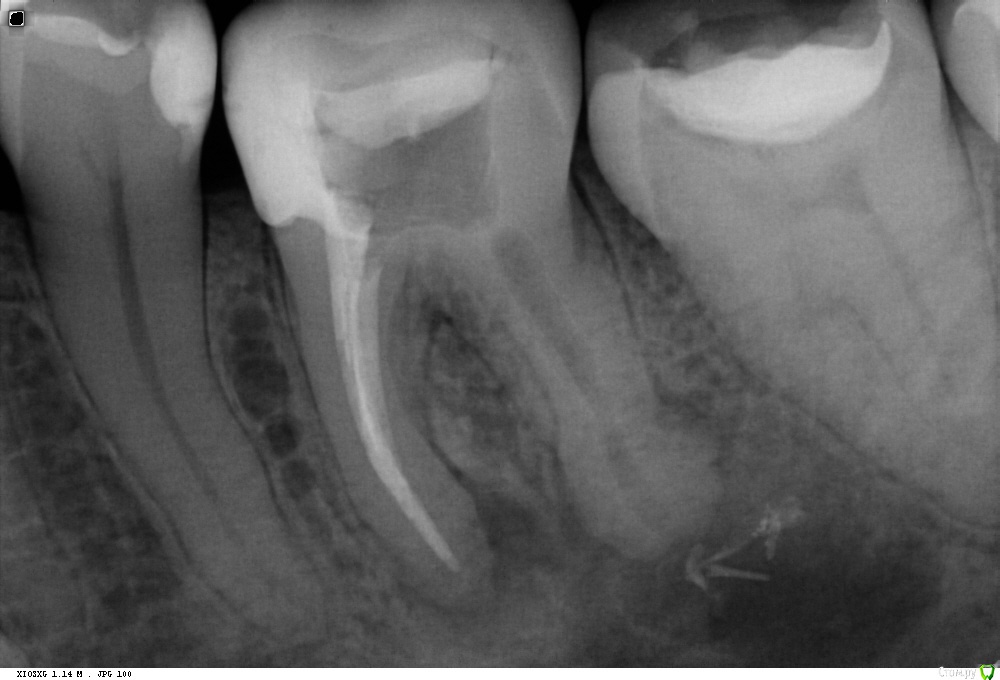

St. Опубликовано 30 января, 2018 Поделиться Опубликовано 30 января, 2018 До, с инструментом и после. Испортила немного картинку после выведенным силлером Ссылка на комментарий

St. Опубликовано 30 января, 2018 Поделиться Опубликовано 30 января, 2018 Сейчас после повторной распломбировки, апикальный размер больше, такое впечатление что идет активная резорбция там Ссылка на комментарий